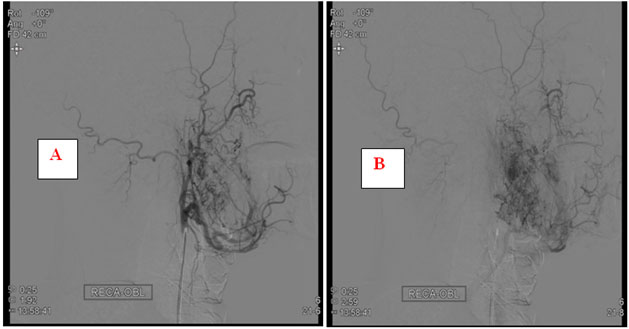

Cerebral digital subtraction angiography revealed moderately vascular right parapharyngeal mass supplied by right facial and internal maxillary artery branches with good cross flow to right cerebral hemisphere via anterior communicating artery and non-visualized upper cervical portion of internal jugular vein (IJV)-likely compressed with no definite involvement of right internal carotid artery (ICA) (Figure 4).

Figure 4: Digital subtraction angiogram images of right external carotid artery showing (A) early phase filling of tumor from right maxillary artery and facial artery (B) late diffuse tumor blush.